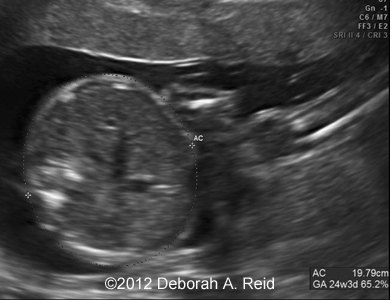

Ultrasound showed left-sided congenital diaphragmatic hernia with mild polyhydramnios.

The left-sided congenital diaphragmatic hernia contained a large portion of the bowel, spleen, stomach and the tip of the left lobe of the liver. In addition to the congenital diaphragmatic hernia, a sub-diaphragmatic sequestration was also noted which was confirmed by MRI.

Figure 1-10: The left-sided congenital diaphragmatic hernia contained a large portion of the bowel, spleen, stomach and the tip of the left lobe of the liver